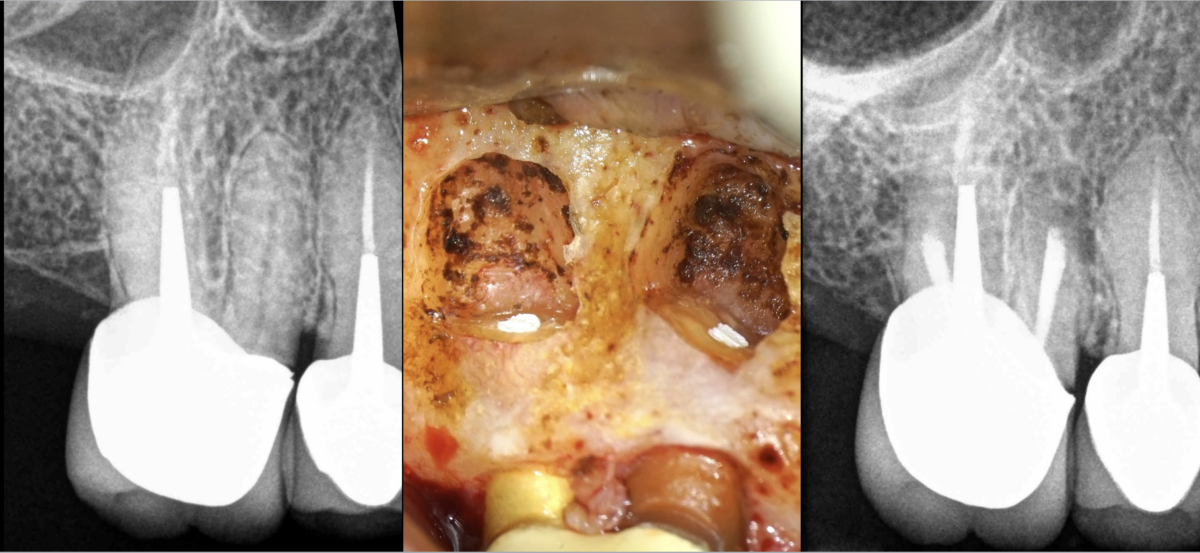

🦷 Cas clinique :

- 𝐏𝐮𝐥𝐩𝐞 𝐩𝐫𝐞́𝐜𝐞́𝐝𝐞𝐦𝐦𝐞𝐧𝐭 𝐭𝐫𝐚𝐢𝐭𝐞́𝐞 (en tout cas dans le canal P)

- 𝐏𝐚𝐫𝐨𝐝𝐨𝐧𝐭𝐢𝐭𝐞 𝐚𝐩𝐢𝐜𝐚𝐥𝐞 𝐬𝐲𝐦𝐩𝐭𝐨𝐦𝐚𝐭𝐢𝐪𝐮𝐞 (lésions apicales des racines MV DV)

- 𝐂𝐡𝐢𝐫𝐮𝐫𝐠𝐢𝐞 𝐞𝐧𝐝𝐨𝐝𝐨𝐧𝐭𝐢𝐪𝐮𝐞 des canaux 𝐌𝐕𝟏 𝐌𝐕𝟐 (ainsi que 𝐥’𝐢𝐬𝐭𝐡𝐦𝐞 les joignant) et 𝐃𝐕

🔹 𝐋𝐞 𝐩𝐫𝐨𝐠𝐧𝐨𝐬𝐭𝐢𝐜 𝐝𝐞 𝐠𝐮𝐞́𝐫𝐢𝐬𝐨𝐧 𝐨𝐬𝐬𝐞𝐮𝐬𝐞 𝐞𝐬𝐭 𝐝’𝐞𝐧𝐯𝐢𝐫𝐨𝐧 𝟗𝟎 %

📅 𝐑𝐃𝐕 𝐝𝐚𝐧𝐬 𝟔 𝐦𝐨𝐢𝐬 𝐩𝐮𝐢𝐬 𝟏 𝐚𝐧 𝐩𝐨𝐮𝐫 𝐥𝐞 𝐜𝐨𝐧𝐭𝐫𝐨̂𝐥𝐞.